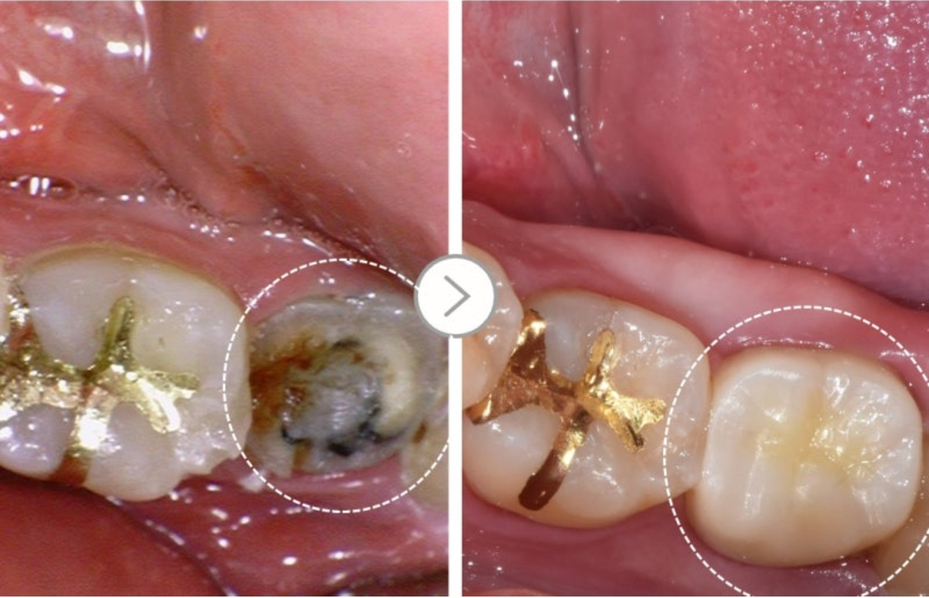

Hãy cùng xem trường hợp bệnh nhân dưới đây.

Những lỗ sâu đen có thể nhìn thấy rõ ràng

bên trong chiếc răng nơi mão răng bị rơi ra.

▲ Sâu răng bên trong thân răng

Trong trường hợp này, loại bỏ răng sâu

lấp đầy bằng vật liệu nha khoa như resin, sau đó đặt lại mão răng.

Trong một số trường hợp có thể sử dụng lại mão răng cũ

nhưng trong hầu hết mão răng mới được chế tác và ốp lại

▲ Gắn mão răng mới sau khi điều trị sâu răng